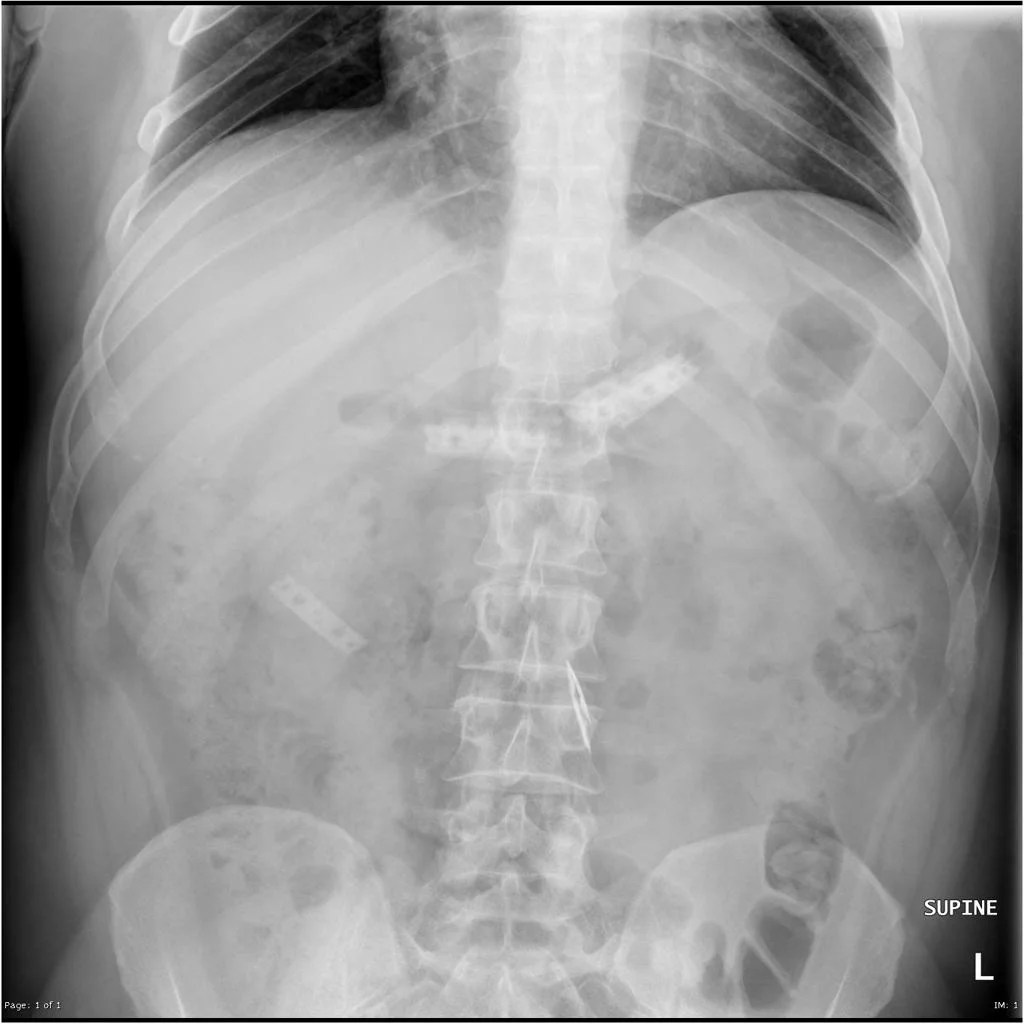

Razor Blade Xray . It is located on the right side of the abdomen and is therefore beyond the stomach. Foreign body ingestion is a common clinical presentation with less than 1% of the cases requiring surgical intervention. X ray showing the razor blades in the small bowel, beyond the reach of a standard upper gastrointestinal endoscope. If a razor blade passes the stomach and duodenum, then it usually passes through the lower gastrointestinal tract without difficulty. The patient presented to the er after accidental ingestion of a razor blade. With a diagnosis of razor blade ingestion causing thoracic esophageal perforation, a decision was taken to pursue operative. In this report, we present a. Multiple radiopaque foreign bodies are demonstrated throughout the abdomen, consistent with ingested razor blades.

In this report, we present a. With a diagnosis of razor blade ingestion causing thoracic esophageal perforation, a decision was taken to pursue operative. Foreign body ingestion is a common clinical presentation with less than 1% of the cases requiring surgical intervention. If a razor blade passes the stomach and duodenum, then it usually passes through the lower gastrointestinal tract without difficulty. It is located on the right side of the abdomen and is therefore beyond the stomach. X ray showing the razor blades in the small bowel, beyond the reach of a standard upper gastrointestinal endoscope. Multiple radiopaque foreign bodies are demonstrated throughout the abdomen, consistent with ingested razor blades. The patient presented to the er after accidental ingestion of a razor blade.